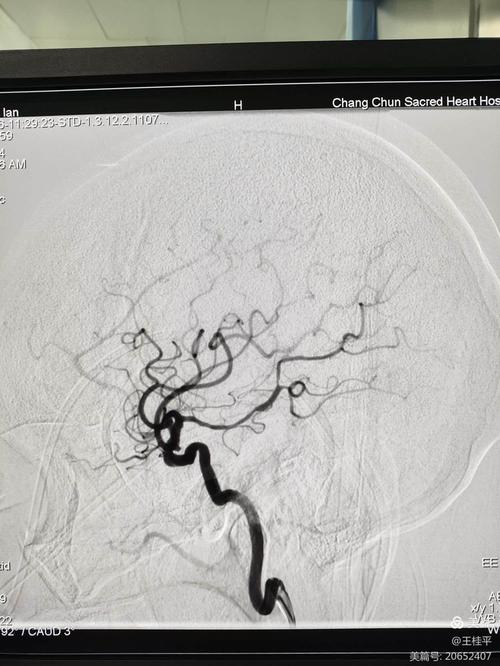

这是一个非常重要且常见的问题。对于脑梗患者,尤其是急性期患者,做CTA(CT血管造影)是非常有必要的,甚至是关键的检查之一。

CTA的主要作用是“看水管”,也就是清晰地显示您脑部血管的情况,对于脑梗患者,它能回答以下几个最关键的问题:

CTA (CT血管造影) 显示血管有无堵塞、狭窄、畸形 速度快,能清晰显示颈部和颅内大血管,对指导急性期治疗(取栓)至关重要。 需要注射造影剂,有少量辐射,对微小血管的显示不如MRA。

DSA (数字减影血管造影) 血管检查的“金标准” 图像分辨率最高,能动态显示血流,同时可进行介入治疗(如取栓、支架植入)。 有创性检查,是导管插入血管,存在一定风险(如出血、感染),费用高,通常在需要做介入治疗时才进行。